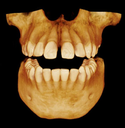

With an image resolution of up to 90 μm, the CS 9300 delivers a superb level of detail that’s ideal for a range of clinical applications, including implants, oral and maxillofacial surgery, orthodontics, and more.

Ability to collimate field of view to suit your diagnostic requirements3D options include Focused field, Single/Dual Jaw, TMJ (2x and 4x), Sinus, and Maxillofacial exams.

Along with its exceptional 3D imaging capabilities, the CS 9300 also features 2D digital panoramic imaging with variable focal trough technology—and can even be upgraded to include one-shot cephalometric imaging.